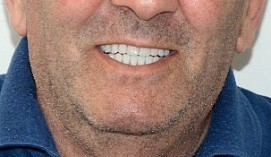

21 работа в портфолио